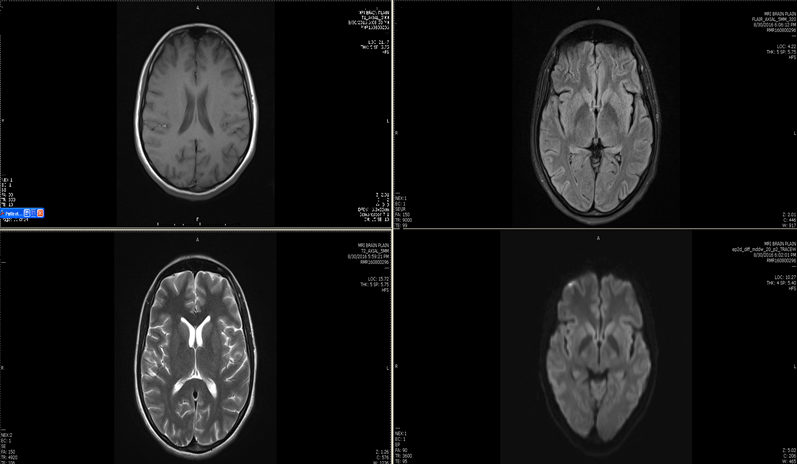

His further blood workup showed increasing trend of CRP level, high procalcitonin level (3.32 ng/ml) and significant positive titer of Widal test (S. Typhi O >1:160 and S. Typhi H >1:640) and positive typhi dot IgM immunoassay for salmonella typhi. MRI brain with contrast study done which was normal (Figure 1). The CSF study was unremarkable and blood culture showed the growth of multi-drug resistant Salmonella typhi.